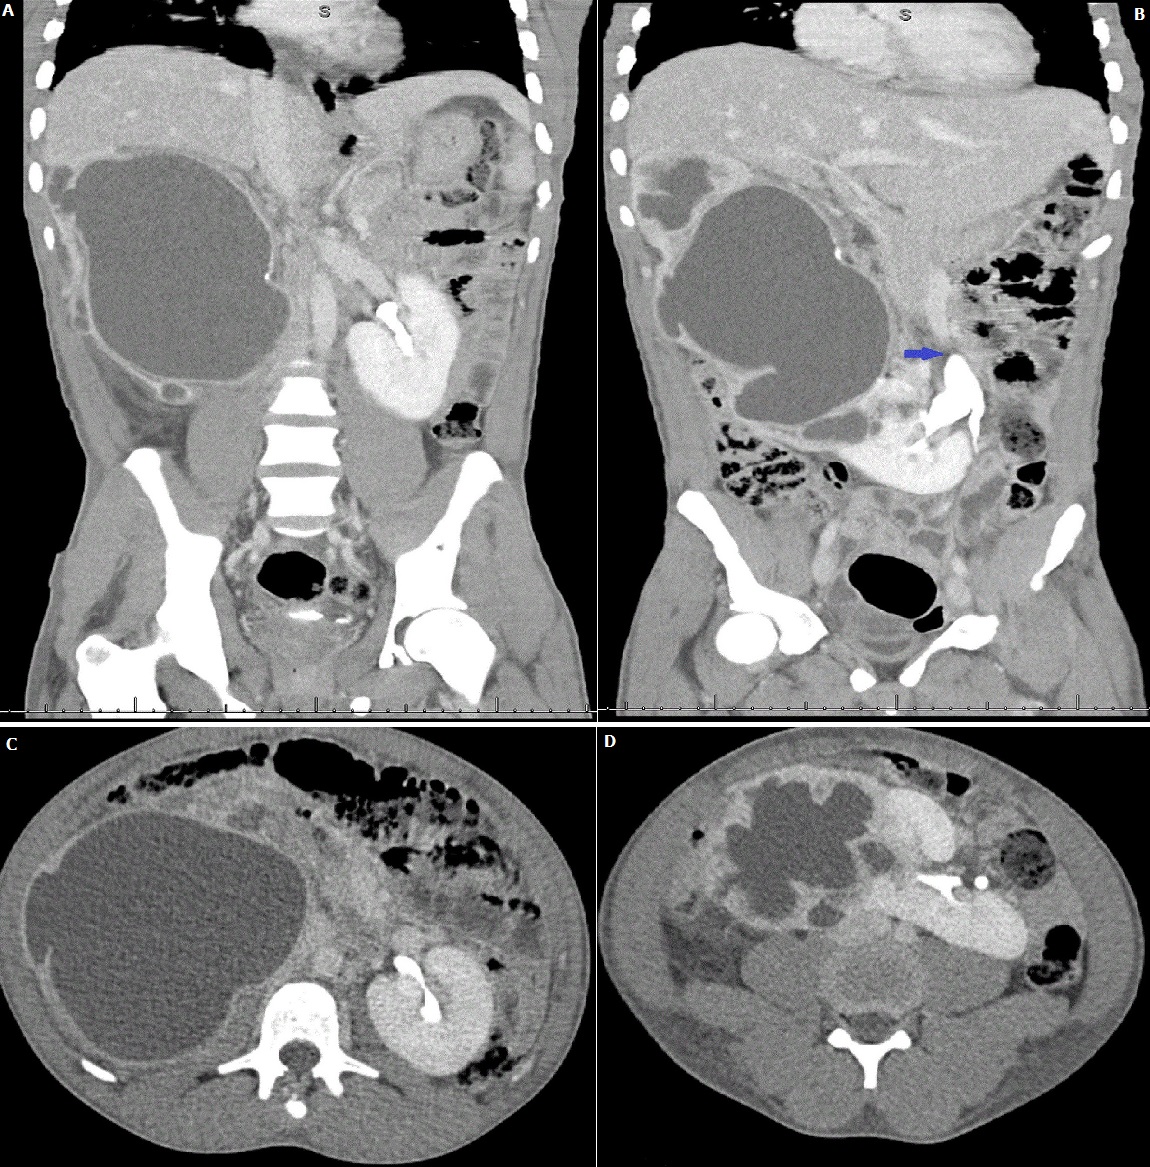

A 21-year-old male presented with a one day history of right flank pain and signs of severe sepsis. The recorded vital signs included a temperature of 39.9° Celsius, blood pressure of 95/65 mmHg and heart rate of 165. The laboratory investigations confirmed a raised C-reactive protein (CRP) of 485 mg/l but it was interesting to note thatthe white cell count and creatinine were respectively normal (5.85 x 109/l; 77 µmol/l). Microbiological investigations confirmed Klebsiella pneumoniae (>106 cfu/mL) on urine culture whilst two blood cultures were negative. Intravenous fluid resuscitation was successful in restoring hemodynamic stability. Amoxicillin/clavulanic acid (1200mg) was administered and continued for seven days after confirmation on antibiotic sensitivity testing. After ultrasonography confirmed severe right hydronephrosis, a contrasted computed tomography (CT) scan confirmed a horseshoe kidney (A, B, C, D) with an obstructed right-sided renalmoiety secondary to right pelvi-ureteric junction (PUJ) obstruction (B) and urothelial enhancement suggestive of an infected collecting system. Horseshoe kidneys are the most common congenital renal abnormality with an incidence of 1:400-600. It is commonly asyptomatic and rarely require interventionunless treating complications such as ureteral obstruction (PUJ), urinary tract infections, urolithiasis andWilms Tumour. It is associated with Trisomy 18 and females with Turner syndrome. Our patient underwent a right percutaneous nephrostomy (PCN) and 500 millilitres of infected urine were aspirated. He made a complete recovery at discharge. An interval MAG3 renogram confirmed that both moeities had good and excretion. A pelvi-ureteric junction repair will be performed after 6 weeks.